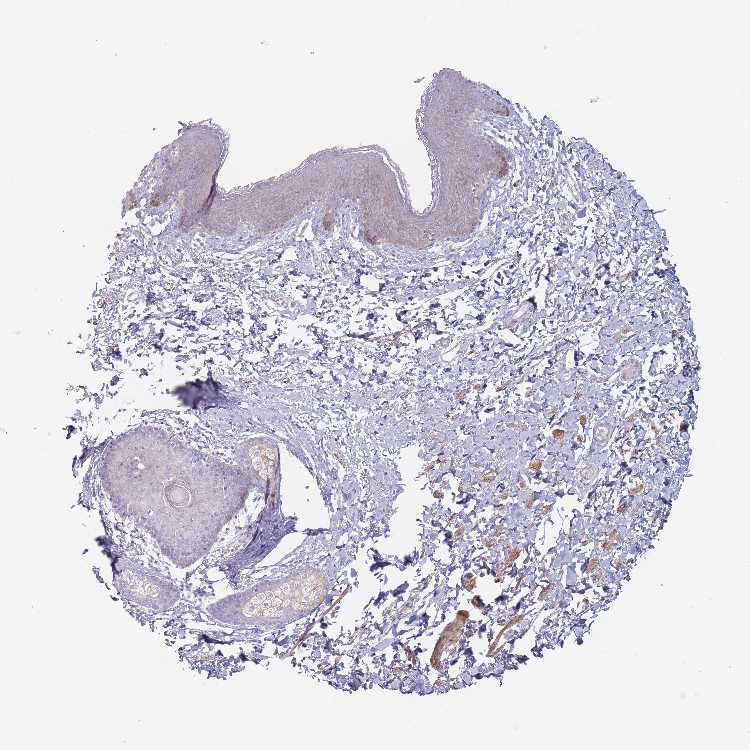

SKIN 1 - Antibody stainingi

Antibody staining in the annotated cell types in the current human tissue is reported as not detected, low, medium, or high, based on conventional immunohistochemistry profiling in selected tissues. This score is based on the combination of the staining intensity and fraction of stained cells.

Each image is clickable and will lead to virtual microscopy that enables deeper exploration of all samples and also displays staining intensity scores, fraction scores and subcellular localization as well as patient and tissue information for each sample.

Antibody HPA048606Antibody HPA059863

Langerhans Not detectedNot detected

Fibroblasts Not detectedMedium

Keratinocytes Not detectedNot detected

Melanocytes Not detectedLow